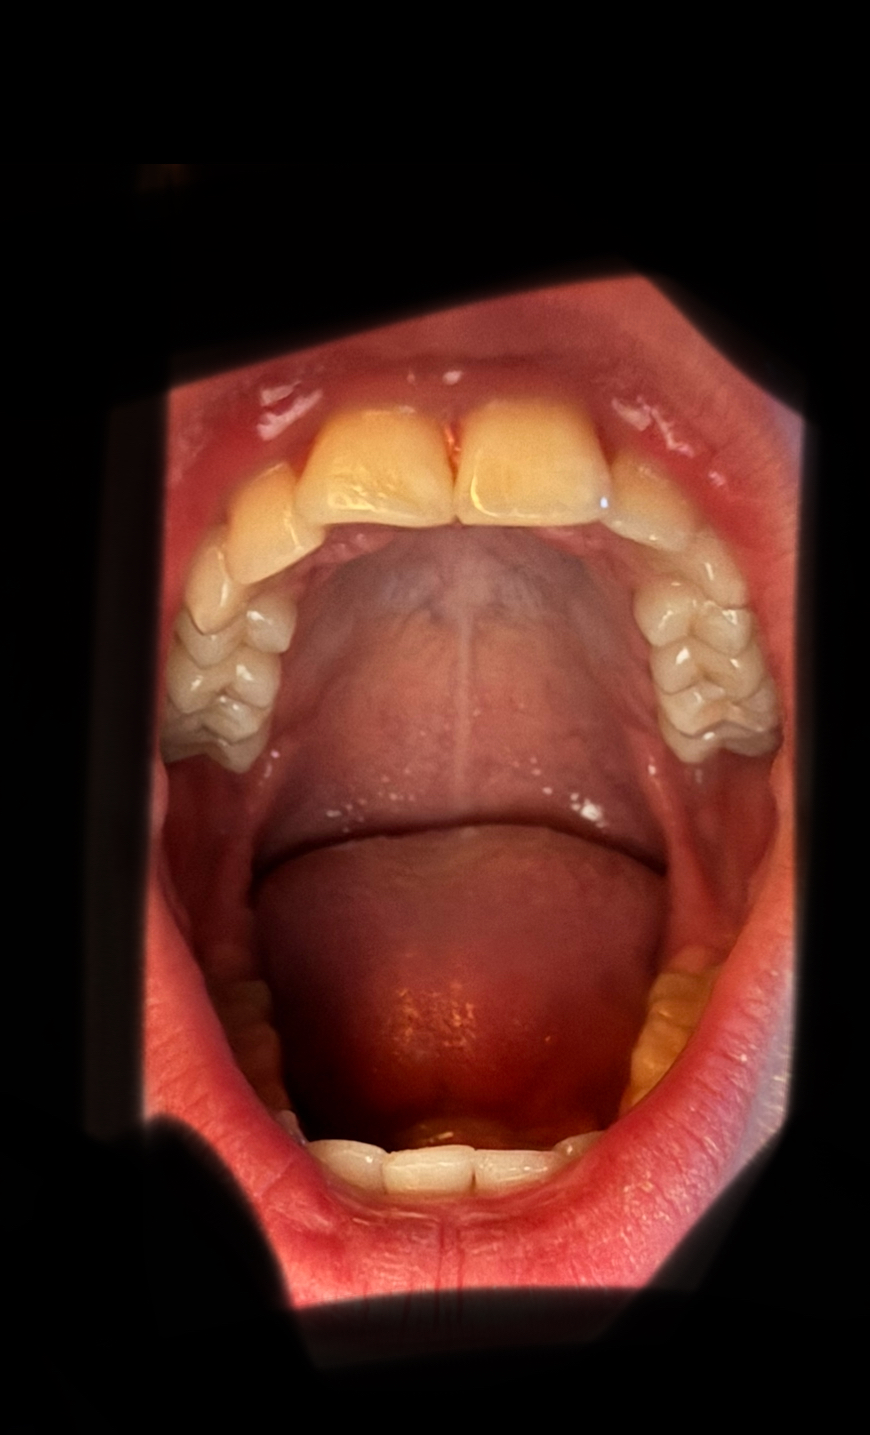

you should stfuView attachment 4320095View attachment 4320098View attachment 4320096 I have always had a short mandible and recessed chin since I was mouth breathing and malnourished since birth, I went to a dentist and got night braces that jutted my teeth forward. I have just got it confirmed that I should stop with it. Should I get a palate expander or braces or something else orthodontic related?